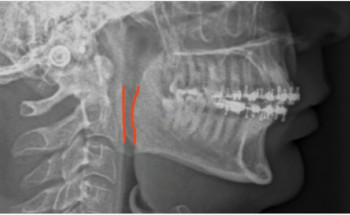

أنهت مدينةُ الملك سعود الطبية عضو تجمع الرياض الصحي الأول، معاناةَ أربعيني من اضطراب النوم، بإجراء تصحيح التطابق الهيكلي بتقديم الفكين العلوي والسفلي والذقن؛ إذ نجحت العملية بالعلاج وظيفيًّا بزيادة حجم المساحة الخلفية للمجرى الهوائي.وأوضحت ...